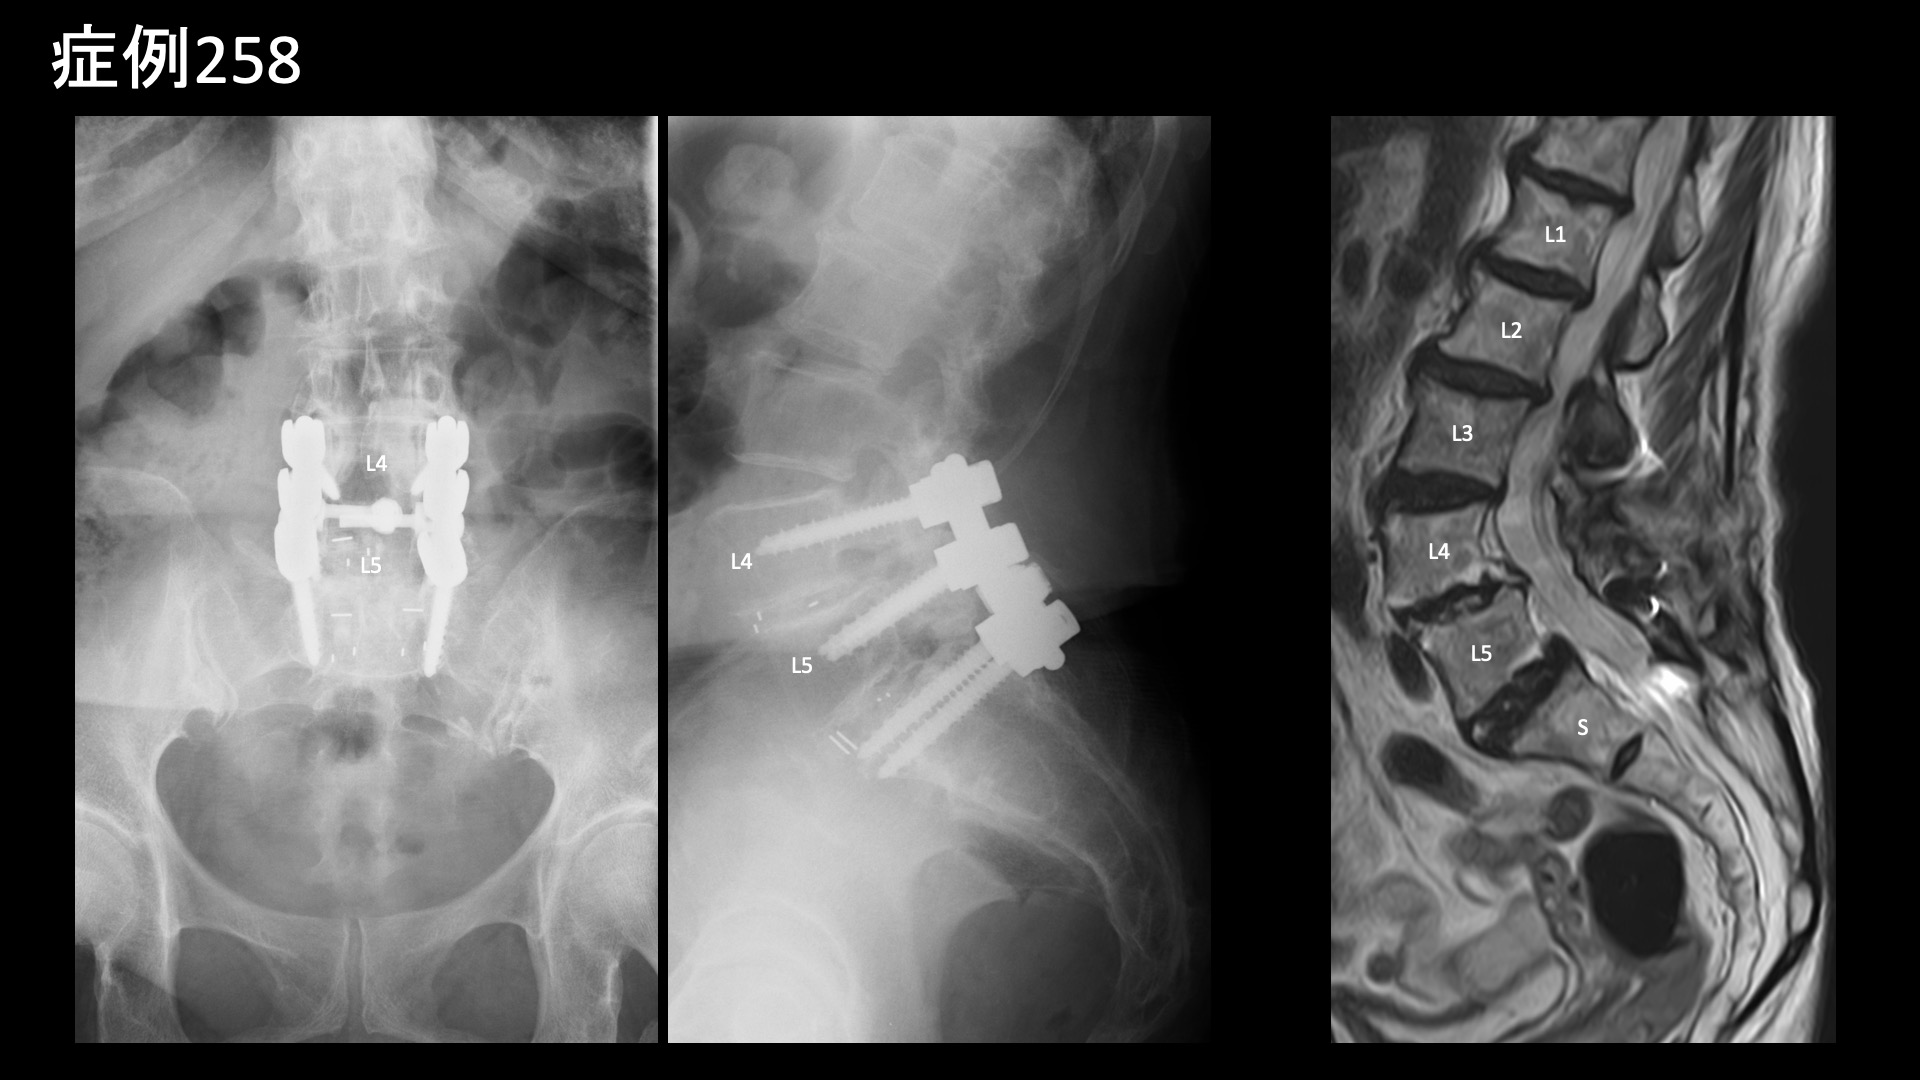

腰の可動域をチェックすると、前屈以外は全て高度に制限されていました。股関節の内外旋は可能でしたが、外旋時に鼠径部痛が誘発されました。L3/4,L4/5椎間関節、棘間靭帯に圧痛を認めました。さらに、上後腸骨棘(PSIS)、梨状筋、鼠径部、大腿外側に強い圧痛を認めました。レントゲンでは腰椎固定術後の様子を確認したほか、仙腸関節の骨硬化像、軽度の股関節変形を認めました。以上より総合的に判断し、仙腸関節障害、両側変形性股関節症、筋・筋膜性疼痛症候群、腰椎性腰痛(椎間関節炎、棘間靭帯炎)および両側坐骨神経障害(腰椎固定術後、脊柱管狭窄)の合併状態と診断しました。重症、高齢であり、複数回の治療を要する可能性があること、一定の症状は残存すること(特にしびれなどの感覚障害)などを十分ご理解いただいたうえでモヤモヤ血管(病的新生血管)に対する運動器カテーテル治療(微細動脈塞栓術)を受けていただきました。

固定術近傍を含めて腰椎レベル~股関節周囲レベルの両側併せて20か所程度の血管を治療しました。特に苦痛なく45分程度で終了しました。